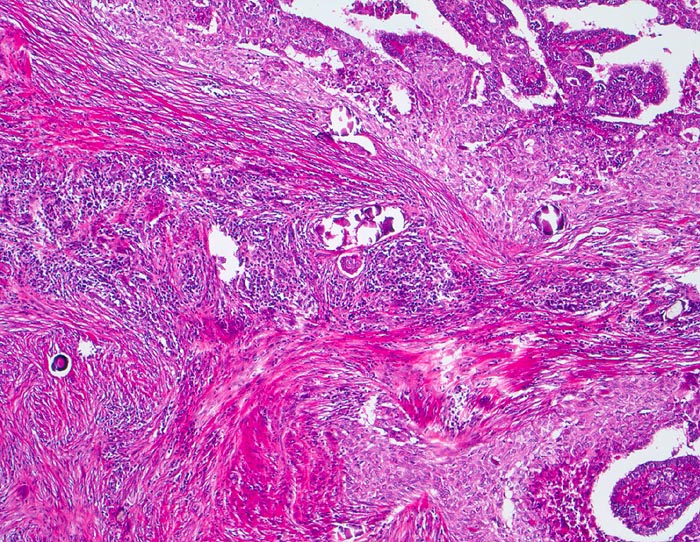

PathoPic – image database / PathoPic ID 3810 - papilläres Schilddrüsenkarzinom diffus sklerosierende Variante

papilläres Schilddrüsenkarzinom diffus sklerosierende Variante

Infiltration der Schilddrüse durch ein papilläres Karzinom mit teils epidermoider Architektur. Auffällige Stromasklerose mit lymphozytärem Entzündungsinfiltrat. Zahlreiche Psammomkörperchen.

Das diffus sklerosierende papilläre Karzinom ist gekennzeichnet durch eine diffuse Infiltration der gesamten Schilddrüse mit Lymphangiosis carcinomatosa begleitet von einer deutlichen Sklerose und chronischen Entzündung. Dieser Tumortyp tritt bevorzugt bei jüngeren Patienten auf und hat eine schlechte Prognose. Plattenepithelmetaplasien treten in bis zu 7% der Schilddrüsenkarzinome auf.